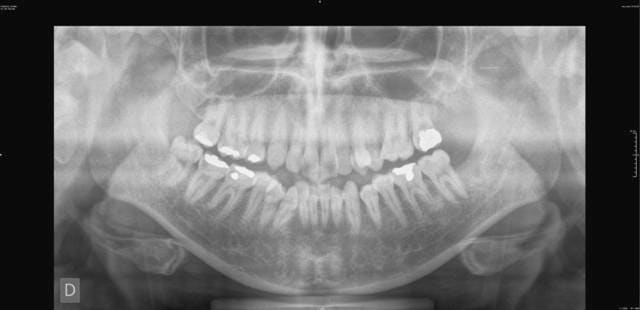

je viens de recevoir un cas d'orthodontie un peu copmliqué et je veux vos suggessions merci

patiente age 26 ans

profil hyperdivergent

la 24 est absente

vous trouvez ci joint les photos

Les caries ont elle été traitées, sur le pano, ça ne semble pas brillant sur le secteur postérieur...